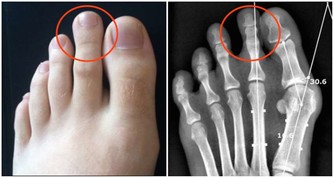

(圖片翻攝自toutiao) 02另一種則是牙齒出現了或深或淺的齲壞,從外面看就表現為一個黑點,通常位於窩溝點隙(牙面上點狀或線狀凹陷)。齲齒的罪魁禍首是口腔中的某些細菌,但它們破壞牙齒也是需要時間的,從初期的變色到最終形成齲洞,通常需要1年半到兩年。在此期間,我們多留心自己的牙齒,完全可能把齲壞扼殺在萌芽階段。如何才能及時發現這種隱匿的蛀牙呢?找位好牙醫,半年檢查牙齒!

(圖片翻攝自toutiao) 一旦確認牙齒上的小黑點是齲齒就應該儘早修補,以阻止病變的發展。如果任由其繼續發展就會變成明顯的齲洞,這時患者會對冷熱酸甜等食物刺激敏感;當損傷進一步到達牙髓(即老百姓說的「牙神經」),就會疼痛難忍,嚴重影響日常生活。臨床上見到很多人都會等到牙痛得受不了,才到醫院就診。這時通常不能靠單純補牙來解決問題,可能還要做根管治療甚至拔除患牙、進行假牙修復,費時費力又費錢,人還遭罪,可謂「小洞不補,大洞吃苦」。 因此,平時應注意自檢,觀察牙齒顏色、形狀、質地的變化,還要每半年進行全面的口腔檢查,如果有齲齒,就應該早發現早治療。 日常護牙小貼士 ①、正確的日常刷牙方法 每天用上10分鐘刷牙,早晚各5分鐘。如果有條件的話,刷牙之後使用牙線清潔牙縫。每隔半年到一年到專業的醫療機構清洗牙齒,因為有些地方是牙刷所不能到達的。